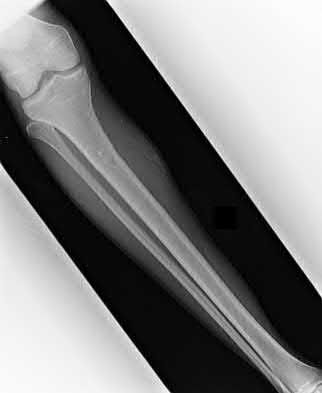

1. # A 32-year-old male sustains the injury shown in Figure A and undergoes treatment as shown in Figure B. Following placement of this implant, what is the best technique to confirm it is not too proud proximally?

The safe zone for tibial nail placement as seen on radiographs is just medial to the lateral tibial spine on the anteroposterior radiograph and immediately adjacent and anterior to the articular surface as visualized on the lateral radiograph.

Tornetta et al specifically located the safe zone for nail entry in a study using fresh frozen cadaver knees. The authors found that the safe zone for nail placement is located 9.1+/-5 millimeters lateral to the midline of the plateau and three millimeters lateral to the center of the tibial tubercle. The width of the safe zone averaged 22.9 millimeters and was as narrow as 12.6 millimeters.

The starting point of the of the nail can be best viewed on the lateral knee radiograph, an example of which is shown in Illustration A. Illustration B shows the "sweet spot" for nail insertion as defined by Tornetta.